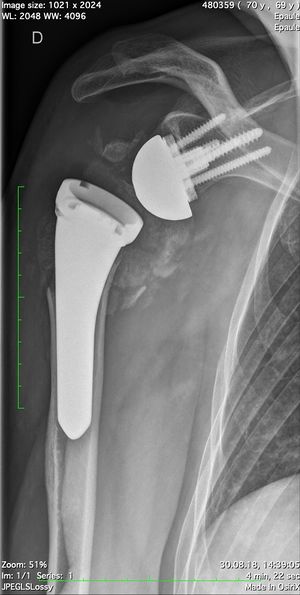

Acute proximal humerus fracture

Reverse shoulder arthroplasty is a more reliable treatment than hemiarthroplasty for complex proximal humerus fractures at least in elderly patients because its functional outcomes appear to depend less on tuberosity healing and rotator cuff integrity (Figure).[90]

Reverse shoulder athroplasty for fracture. Frontal, axial and lateral Lamy radiographs after a reverse total shoulder implant. Note the lower positioning of the glenoid baseplate, the satisfactory reconstruction of the tuberosities, and the absence of cement at the autograft level.